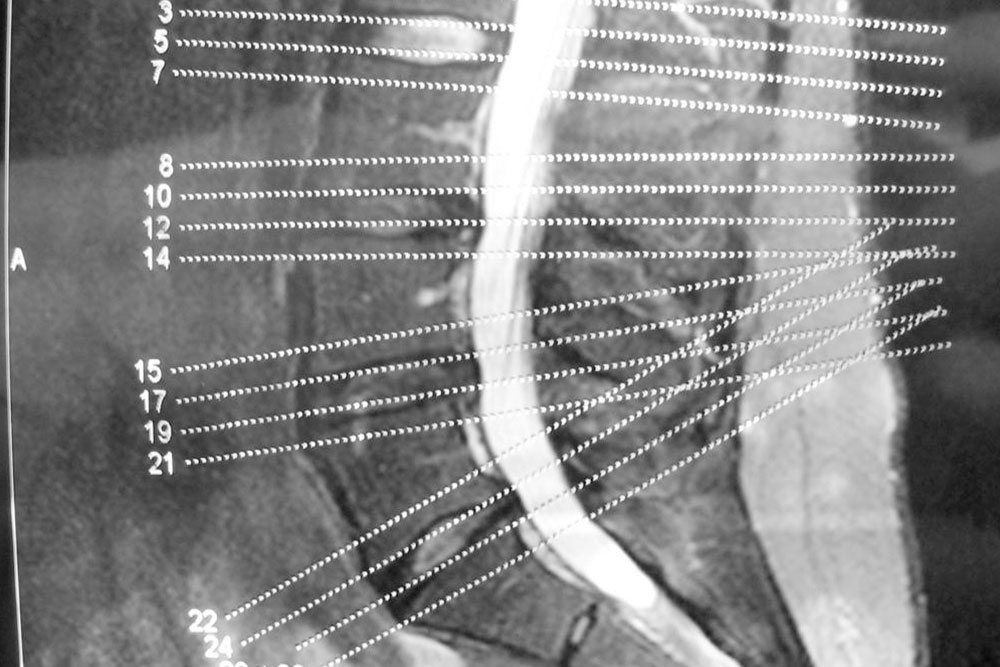

A brief overview of degenerative disc and joint disease

When you mention the term degenerative disease, it refers to the gradual deterioration of the body tissues or cells over the years due to the natural aging process. As we age, our spine starts giving in to the stress of providing flexibility and support to our back. The components of the spine start deteriorating slowly, and you will experience back pain and stiffness in the spine.